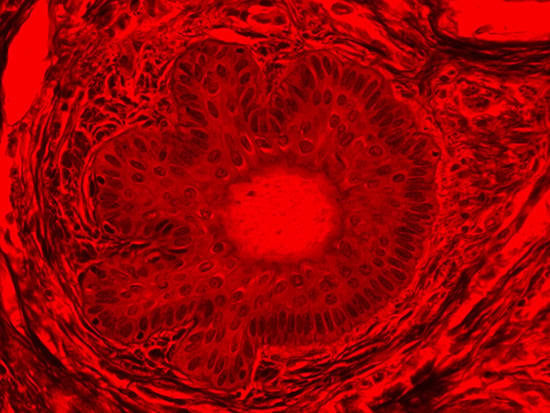

Masson's trichrome stain is incredibly effective in differentiating cells and their components from the surrounding connective tissues. One of the most common stain types, which has been used on the dermal tissue sample seen in the images within this article, yields a number of colors where cell nuclei appear dark red, collagen and other tissues appear green or blue, and cell cytoplasm appear red/purple (Jones, 2010). These stains have been imaged under brightfield and darkfield illumination, and then again with specific filters to selectively focus on the cellular constituents of the epidermis. The primary application for the epidermal trichrome stains is differentiating healthy collagen and muscles from connective tissues onset with tumorigenesis. Typically the tumors proliferate from muscle cells and fibroblasts deep in the dermal tissue (Blitterswijk, 2010).

Figure 4: Brightfield Image of Dermal Tissue filtered with Red

When comparing Figure 3 with Figure 4, there is once again a significant visual difference. The most obvious feature is the change in color from green to red due to a different hardcoated filter being positioned in the optical path. The less obvious difference is the varying contrast levels caused by the filters at specific regions of the dermal tissue. For example, Figure 3 exhibits a distinct ring at the central region of the cell with additional matter within. In Figure 4, the ring is extremely faint and the internal matter is not visible. With that said, the cell and surrounding dense materials are more evident in Figure 3, whereas the muscle fibers and collagen are more pronounced in Figure 4.